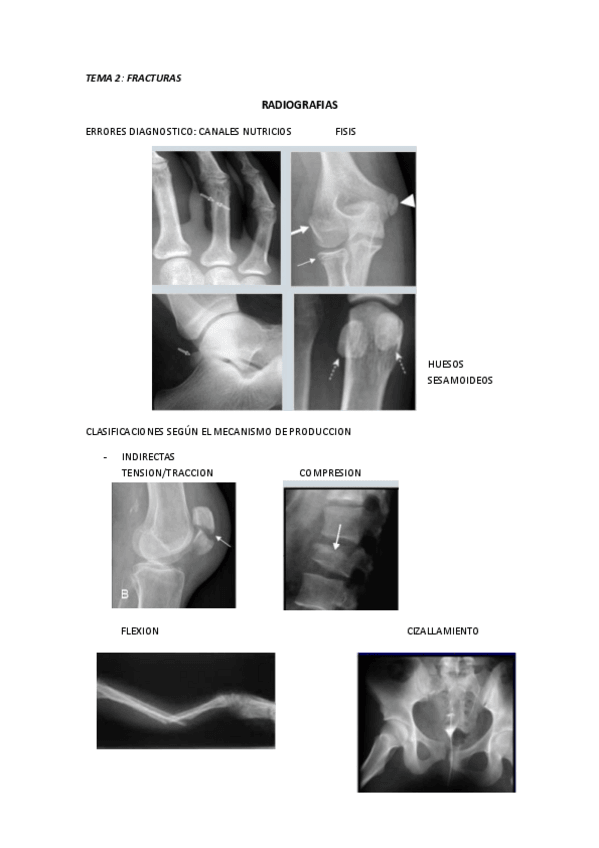

RADIOGRAFIAS PAT.QUIRURGICA

He publicado nuevos apuntes de 2º Patología Quirúrgica: RADIOGRAFIAS PAT.QUIRURGICA

rx-2.pdf

rx-1.pdf

RADIOGRAFIAS

He publicado nuevos apuntes de 2º Patología Quirúrgica: RADIOGRAFIAS

SEMINARIO-RADIOGRAFIAS.pdf

RADIOGRAFIAS.pdf